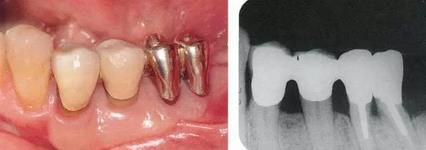

360截圖20170422101945505.jpg

▲圖9-1,2

▲圖9-1 預(yù)定進行正畸治療的患者,下頜磨牙區(qū)的右下6,7牙根接近,并在右下7遠(yuǎn)中存在垂直性骨組織缺損。對牙體狀況、牙周組織、咬合情況進行診斷后制定出的治療方案為:將右下6拔除,對右下7遠(yuǎn)中的骨組織缺失進行再生療法。

▲圖9-2 同部位X光片。右下6遠(yuǎn)中存在牙根接近,較深的骨組織缺損以及II度根分叉病變,所以將其拔除。

360截圖20170422101957225.jpg

▲圖9-3

拔牙后1周的狀態(tài)。愈合后,預(yù)定進行正畸治療穩(wěn)定牙列。